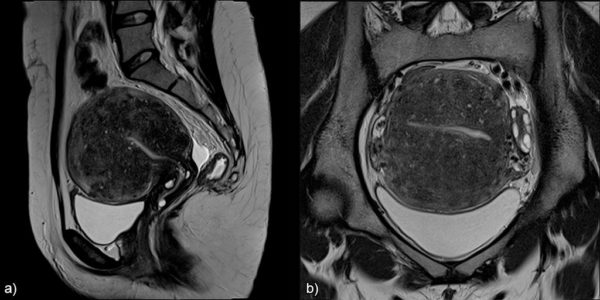

Магнитно-резонансная томография

Выявляют увеличение размеров органа, изменение структуры слизистой оболочки и различную толщину стенок органа.